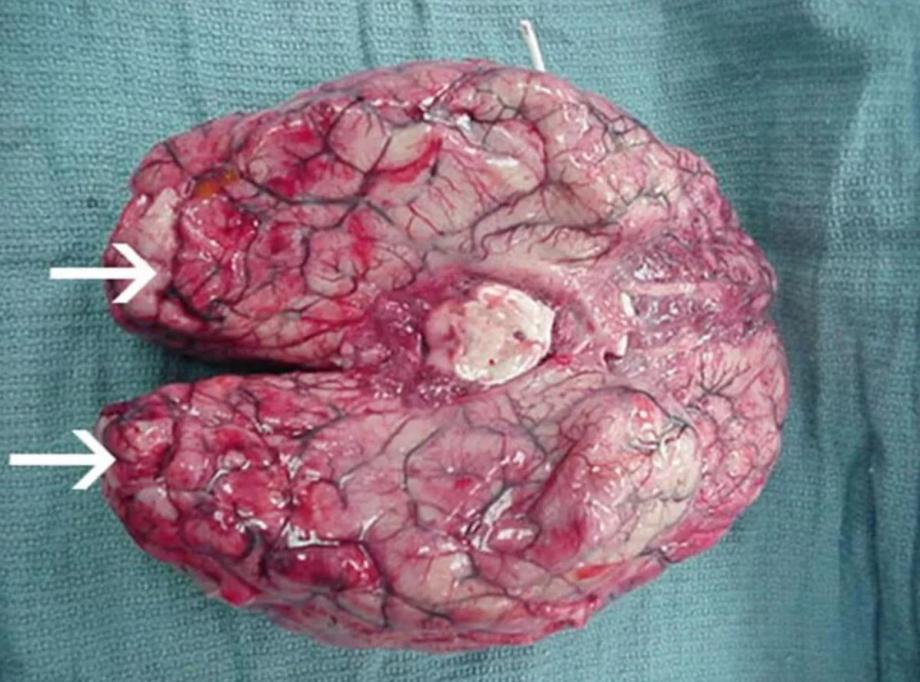

Есть и крайне серьезные заболевания, которых, однако, не стоит бояться, так как они не обитают в России. Так, например, по сообщениям СМИ, 25-летний мужчина попал в больницу с воспалением мозга после посещения пляжа в Израиле. У него обнаружили амебу Naegleria fowleri, которая вызвала неглериоз. В Роспотребнадзоре сообщают, что этой бактерии нет в РФ. В основном она встречается в южных штатах США, Индии и Пакистане.